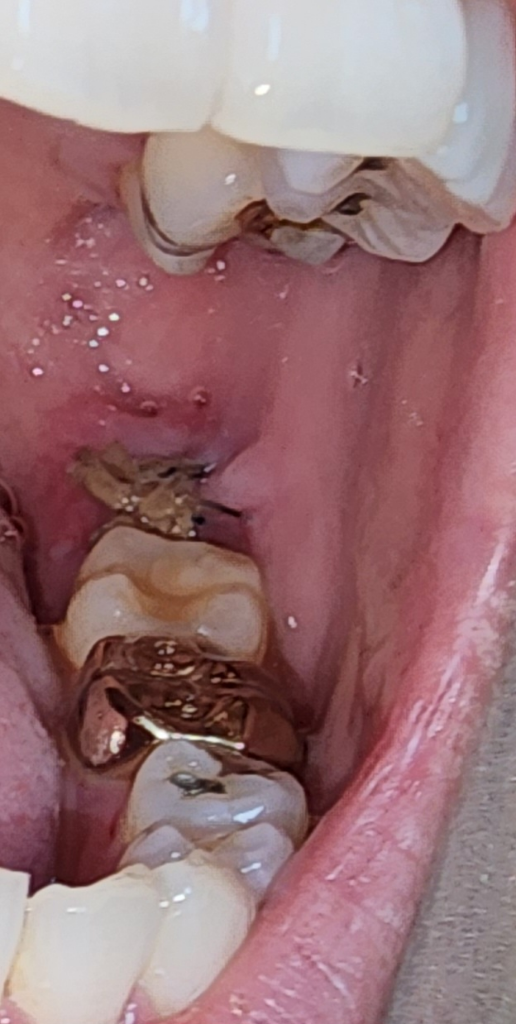

사진 첨부합니다 실밥을 엄청 꼬매주셔서 두쪽 다 드라이소켓같은건 전혀 발생한거같진않아요. 왼쪽 붓기도 아주천천히 빠지고있으나 어금니가아프고 찝힘등으로 잠들기어렵고 밥을못먹는데 어금니통증도 다 자연스러운걸까요? 제 치아상태를보면 그럴수있는건지 궁금합니다.

분명 해당 발치부위빼고 칫솔로 다 살살 닦고 혀클리너도쓰는데 저렇게 더러워요.....

• 1번 째 사진